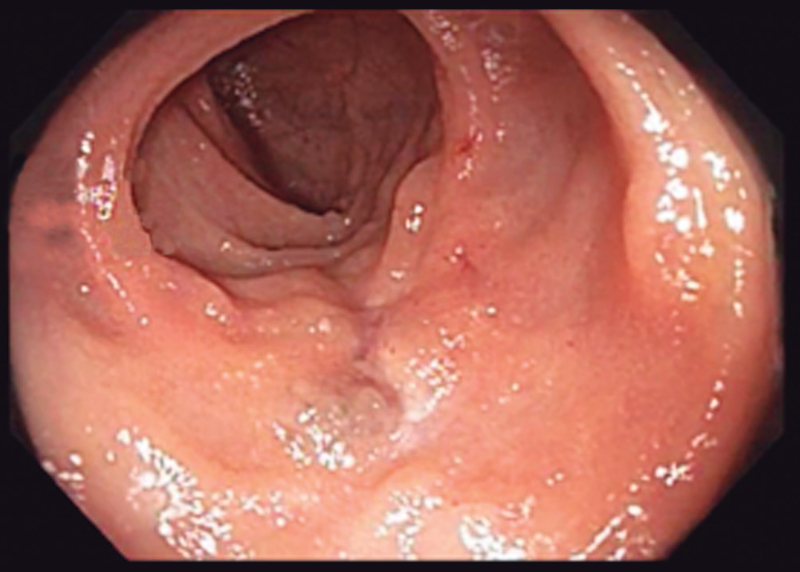

A los seis meses del tratamiento, intercurrió con un nuevo episodio de anemia sintomática. Se realizó enteroscopía anterógrada con doble balón (Fujinon® serie EN-450T5), sin evidencia de lesiones, con marcación del sitio de máxima inserción y enteroscopía retrógrada, evidenciandose en ileon, proximal a la cicatriz del tratamiento previo (Figura 2) una lesión similar a la anterior (Figura 3), de 25 mm de diámetro. Se realizó escleroterapia con polidocanol al 1% (seis mililitros), sin complicaciones.